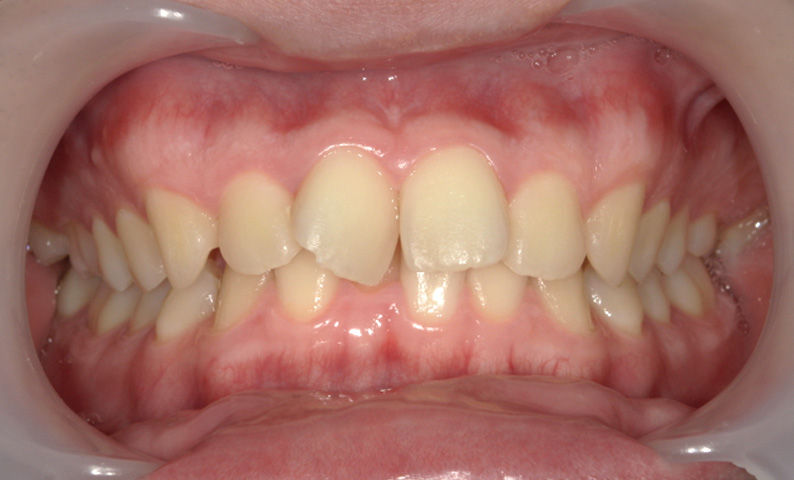

症例_009 「上下の前歯」症例

治療期間:7ヶ月金額:54万円+税20代女性捻転歯一部の反対咬合前歯のガタガタ